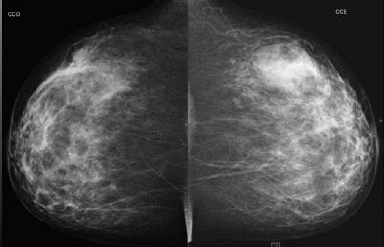

Paciente de 40 anos realizou esta mamografia para rastreio, sendo assintomática. A ultrassonografia realizada em outro serviço, 6 meses antes da mamografia, demonstrou pequeno nódulo hipoecoico de 1,5 cm no QSE da mama direita e nenhuma lesão na mama esquerda. Assinale a alternativa correspondente à hipótese diagnóstica da imagem nodular da mama esquerda observada na mamografia.

Assinale a alternativa que apresenta corretamente o que observa-se na análise das imagens da mamografia.

Uma paciente de 46 anos realizou esta mamografia.

Assinale a alternativa que contém a descrição e a classificação BIRADS correspondente.